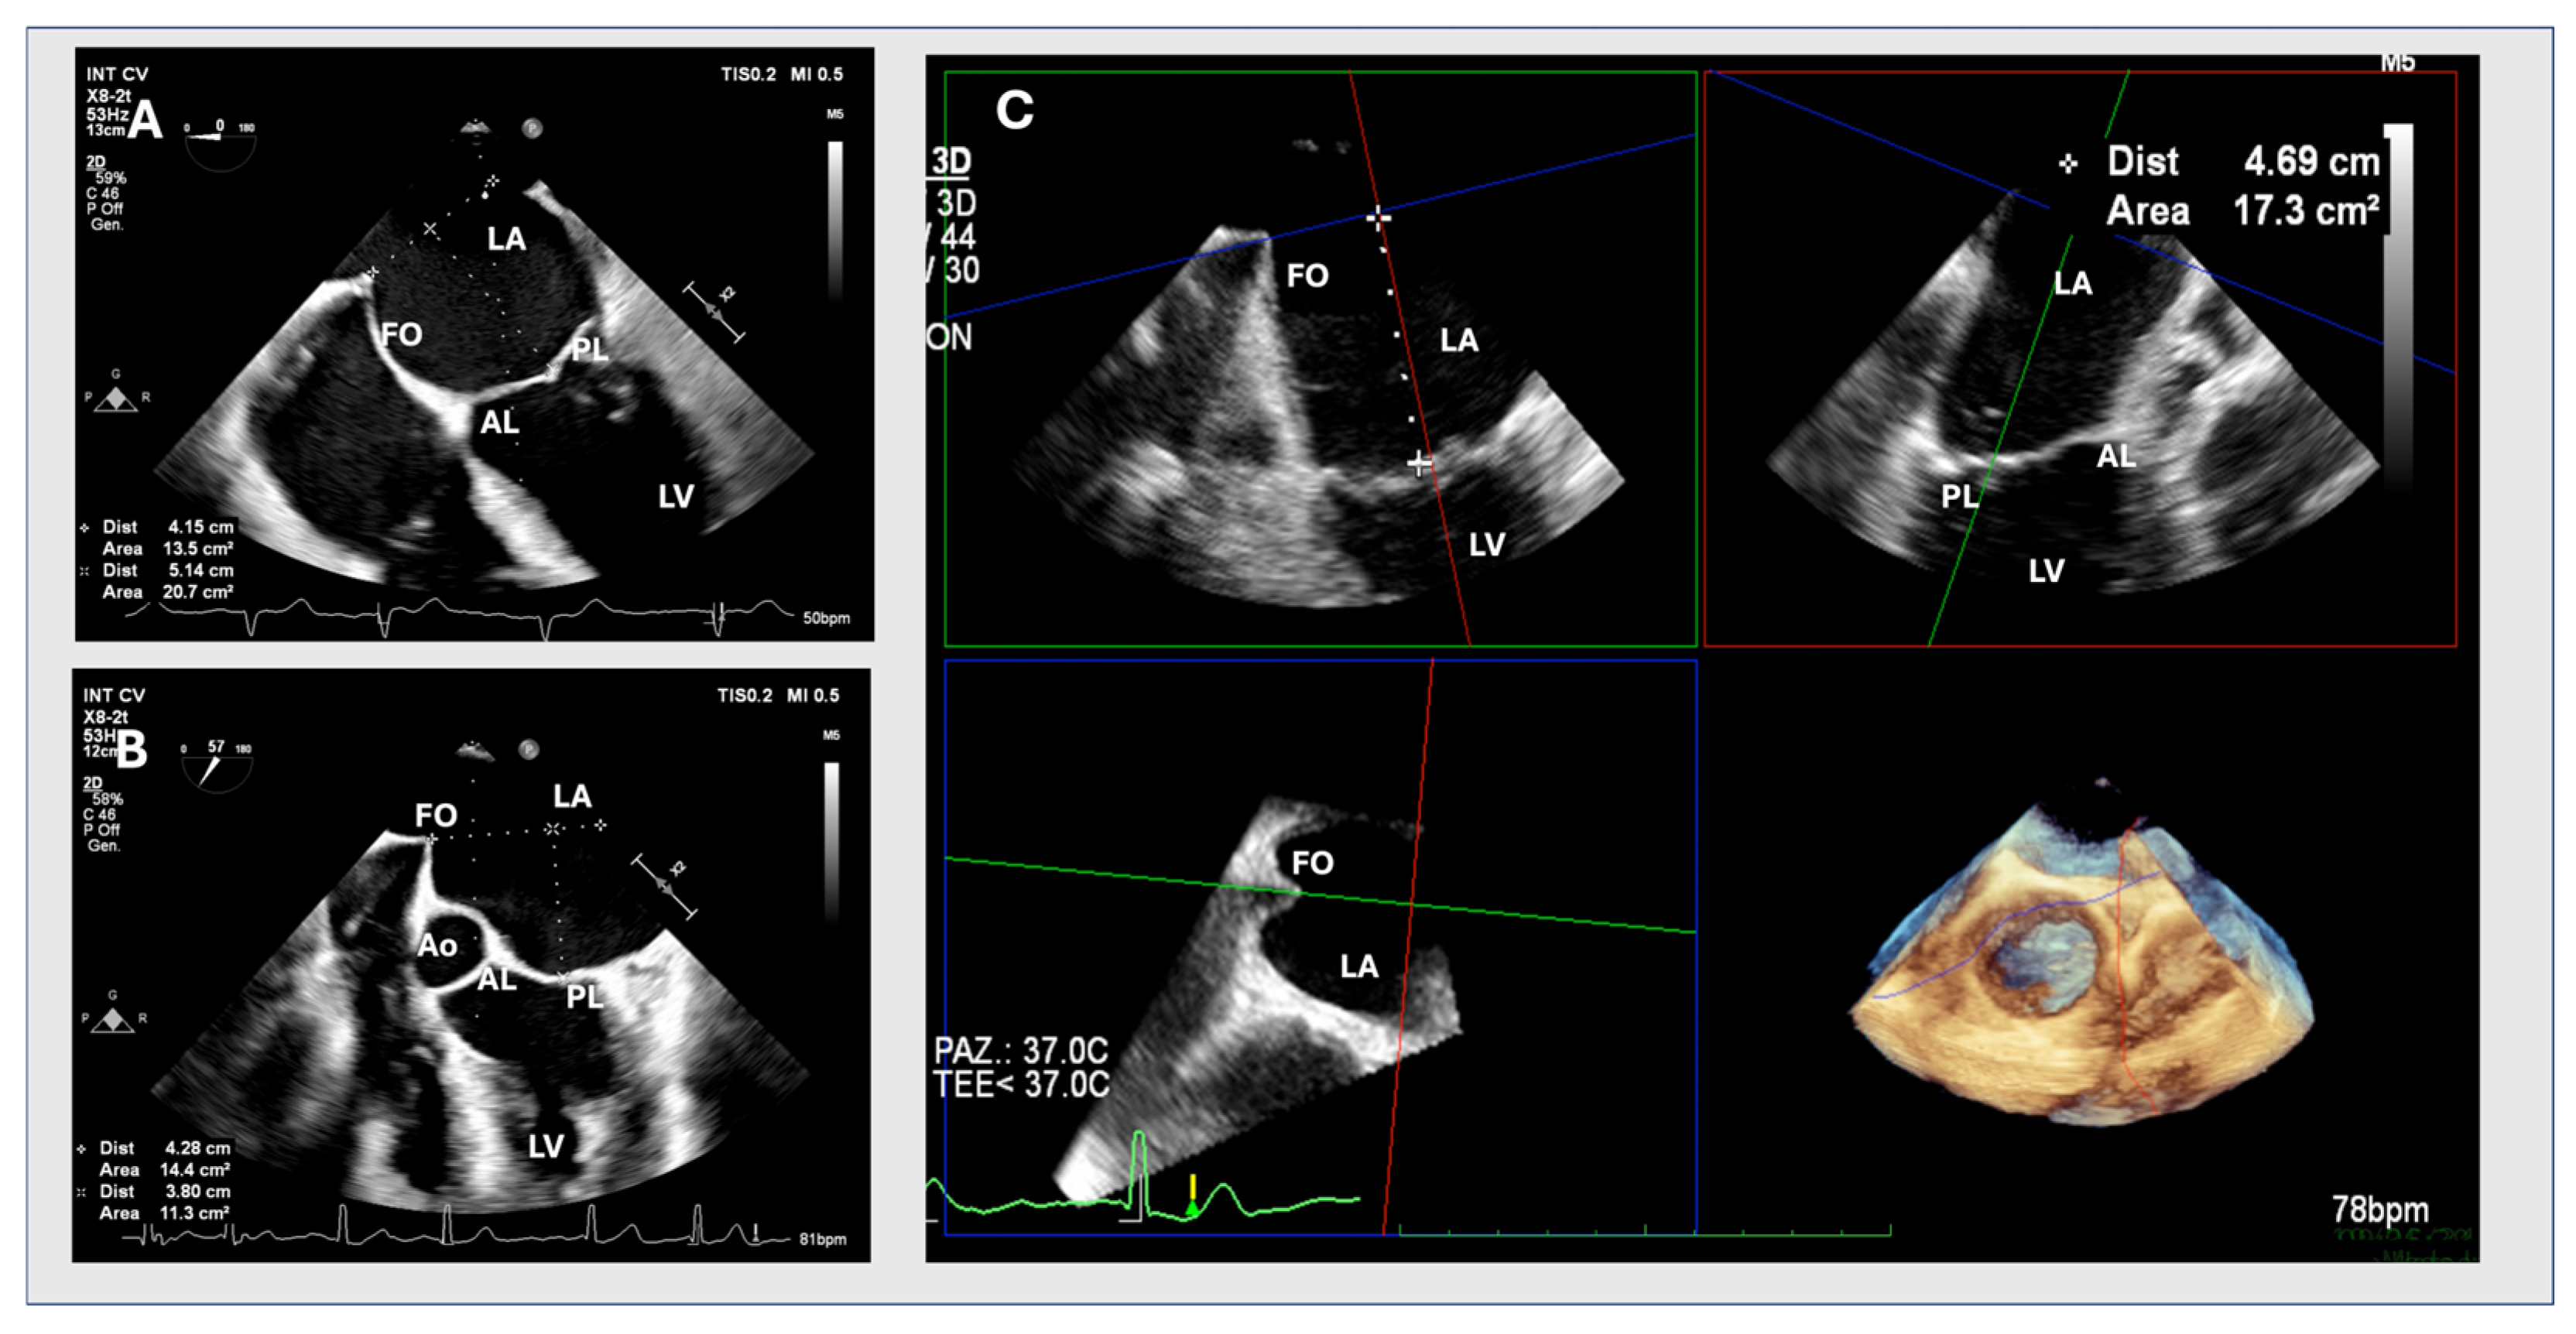

An ME or upper oesophageal (UE) 4-chamber view with slight retroflection of the probe was obtained to include both the FO and the MV leaflet coaptation point. A 2D assessment of tenting height was considered adequate when tenting and the MV leaflet coaptation were clearly seen in the same plane. The view is considered suboptimal if it does not include both structures or if the aortic root is visible in the same plane (Figure 1). Even though every TSP attempt was evaluated in both imaging modalities (2D and 3D with MPR), when the 2D view was considered suboptimal, the site of puncture was chosen based on 3D data. Otherwise, it was based on 2D data.

Figure 1.

Optimal and suboptimal TOE views. (A) shows an accurate determination of tenting height using a two-dimensional upper oesophageal transoesophageal echocardiography view at 0–40°, visualizing the entire fossa ovalis (FO) and mitral valve leaflet coaptation point in a single view during the end-systolic phase. (B) shows a suboptimal view visualizing the FO with only the anterior mitral valve leaflet. AL: anterior leaflet; Ao: aortic valve, FO: fossa ovalis; IAS: interatrial septum; LA: left atrium; LV: left ventricle; PL: posterior leaflet.

Figure 2.

Figures (A,B) show an optimal 2D and suboptimal upper transoesophageal view, respectively. Figure (C) shows a multiplanar three-dimensional reconstruction. AL: anterior leaflet; Ao: aortic valve, FO: fossa ovalis; LA: left atrium; LV: left ventricle; PL: posterior leaflet.